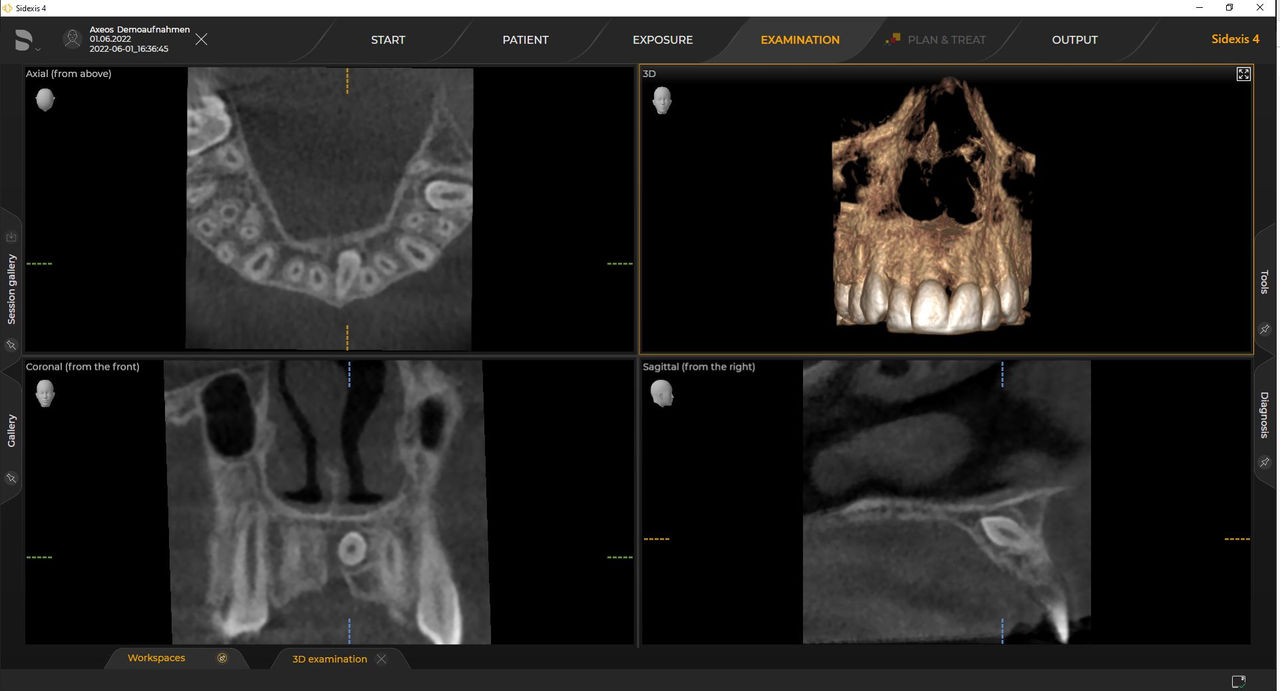

Axeos, el sistema especializado 2D/3D con un gran volumen y alta calidad de imagen para clínicas con una amplia oferta de tratamientos. Desarrollado junto a dentistas y clínicos, Axeos ofrece la gama más completa de funciones de todos los equipos de radiología extraoral de Dentsply Sirona. Además de una excelente calidad de imagen y tamaños de volumen 3D personalizados, el equipo de radiología dental está completamente optimizado para una mayor comodidad del paciente. Axeos no solo proporciona calidad en rendimiento y comodidad, sino también con su galardonado diseño gracias al cajetín de accesorios de bloque de mordida integrado y la luz ambiental.

Los numerosos tamaños de volumen garantizan la flexibilidad en la práctica diaria. Examine un área precisa o evalúe la dentición completa, lo que incluye las ATM

Las unidades 3D de Dentsply Sirona funcionan exclusivamente con Sidexis 4. Sin embargo, la migración de datos de Sidexis XG a Sidexis 4 es muy fácil. Sidexis 4 permite una experiencia digital completa con las últimas herramientas.